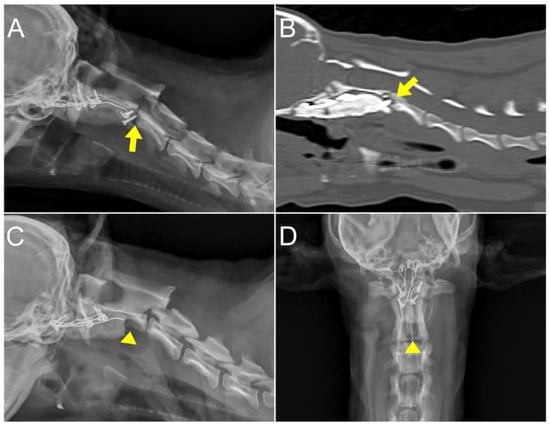

2. Case Description